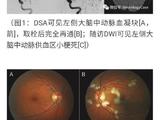

患儿女,41日龄,因“易激惹6d”于2017年4月天津市儿童医院神经内科住院。患儿易激惹、阵发哭闹,精神萎靡,睡眠不安,吃奶差,进行性加重,无抽搐,不伴发热、咳喘、吐泻。当地医院行头颅CT提示“双侧额、颞、顶、枕皮层下区、双侧桥脑、基底节区、丘脑多发性对称性低密度灶”(图1)。患儿为母亲第2胎第2产,胎龄39“周剖宫产出生,否认窒息史,出生体重3.0kg。父母健康,非近亲结婚;胞姐4岁,发育正常。